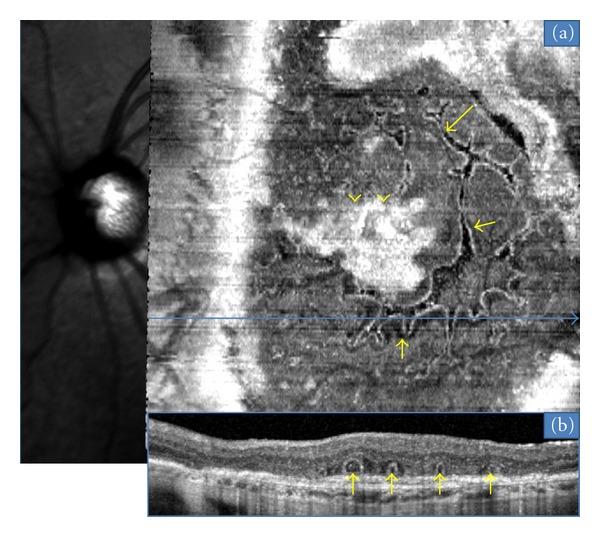

Purpose. "En face" is an emerging imaging technique derived from spectral domain optical coherence tomography (OCT). It produces frontal sections of retinal layers, also called "C-scan OCT." Outer retinal tubulations (ORTs) in age-related macular degeneration (AMD) are a recent finding evidenced by spectral-domain OCT. The aim of this study is to characterize the morphology of ORT according to the form of AMD, using "en-face" spectral domain OCT. Methods. "En face" OCT imaging was prospectively performed in 26 consecutive eyes with AMD that also had ORT. Results. There were 15 neovascular, 8 atrophic, and 3 eyes with a mixed (fibrotic and atrophic) form of AMD. Among the neovascular group, the most frequent tubulation pattern on "en-face" OCT was a branching network emanating from a fibrovascular scar; we term this pattern as "pseudodendritic." It did not require treatment when observed as an isolated finding. In all cases of atrophic AMD, the tubular network was located at the edge of the geographic atrophy area, and formed a "perilesional" pattern. Six atrophic cases showed tubular invaginations inside this area. Conclusion. "En face" OCT is a valuable technique in the diagnosis and followup of macular disease. It revealed the main characteristic patterns of ORT associated with neovascular and atrophic AMD.

目的。“正面成像”是一种源自光谱域光学相干断层扫描(OCT)的新兴成像技术。它能生成视网膜各层的正面图像,也称为“C 扫描 OCT”。年龄相关性黄斑变性(AMD)中的视网膜外层微管(ORTs)是光谱域 OCT 最近发现的现象。本研究的目的是使用“正面成像”光谱域 OCT 根据 AMD 的类型来描述 ORT 的形态。方法。对 26 只连续患有 AMD 且伴有 ORT 的眼睛进行前瞻性“正面成像”OCT 成像。结果。有 15 只新生血管性、8 只萎缩性以及 3 只混合性(纤维化和萎缩性)AMD 眼睛。在新生血管性组中,“正面成像”OCT 上最常见的微管模式是从纤维血管瘢痕发出的分支网络;我们将这种模式称为“假树枝状”。当作为孤立发现观察时不需要治疗。在所有萎缩性 AMD 病例中,管状网络位于地图样萎缩区域的边缘,并形成“病灶周围”模式。6 例萎缩性病例在该区域内显示有管状内陷。结论。“正面成像”OCT 是黄斑疾病诊断和随访中的一项有价值的技术。它揭示了与新生血管性和萎缩性 AMD 相关的 ORT 的主要特征模式。